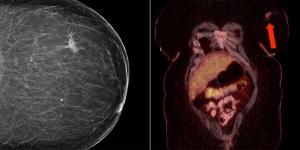

A 41-year-old woman with a past medical history notable for HIV underwent her first screening mammogram, which demonstrated a 1.5-cm irregular focal asymmetry in the left breast. What is your diagnosis?